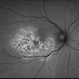

- A 30-year-old male myopic patient presented with sudden loss of vision , on examination he was found to have subretinal hemorrhage and on FFA this picture is seen.